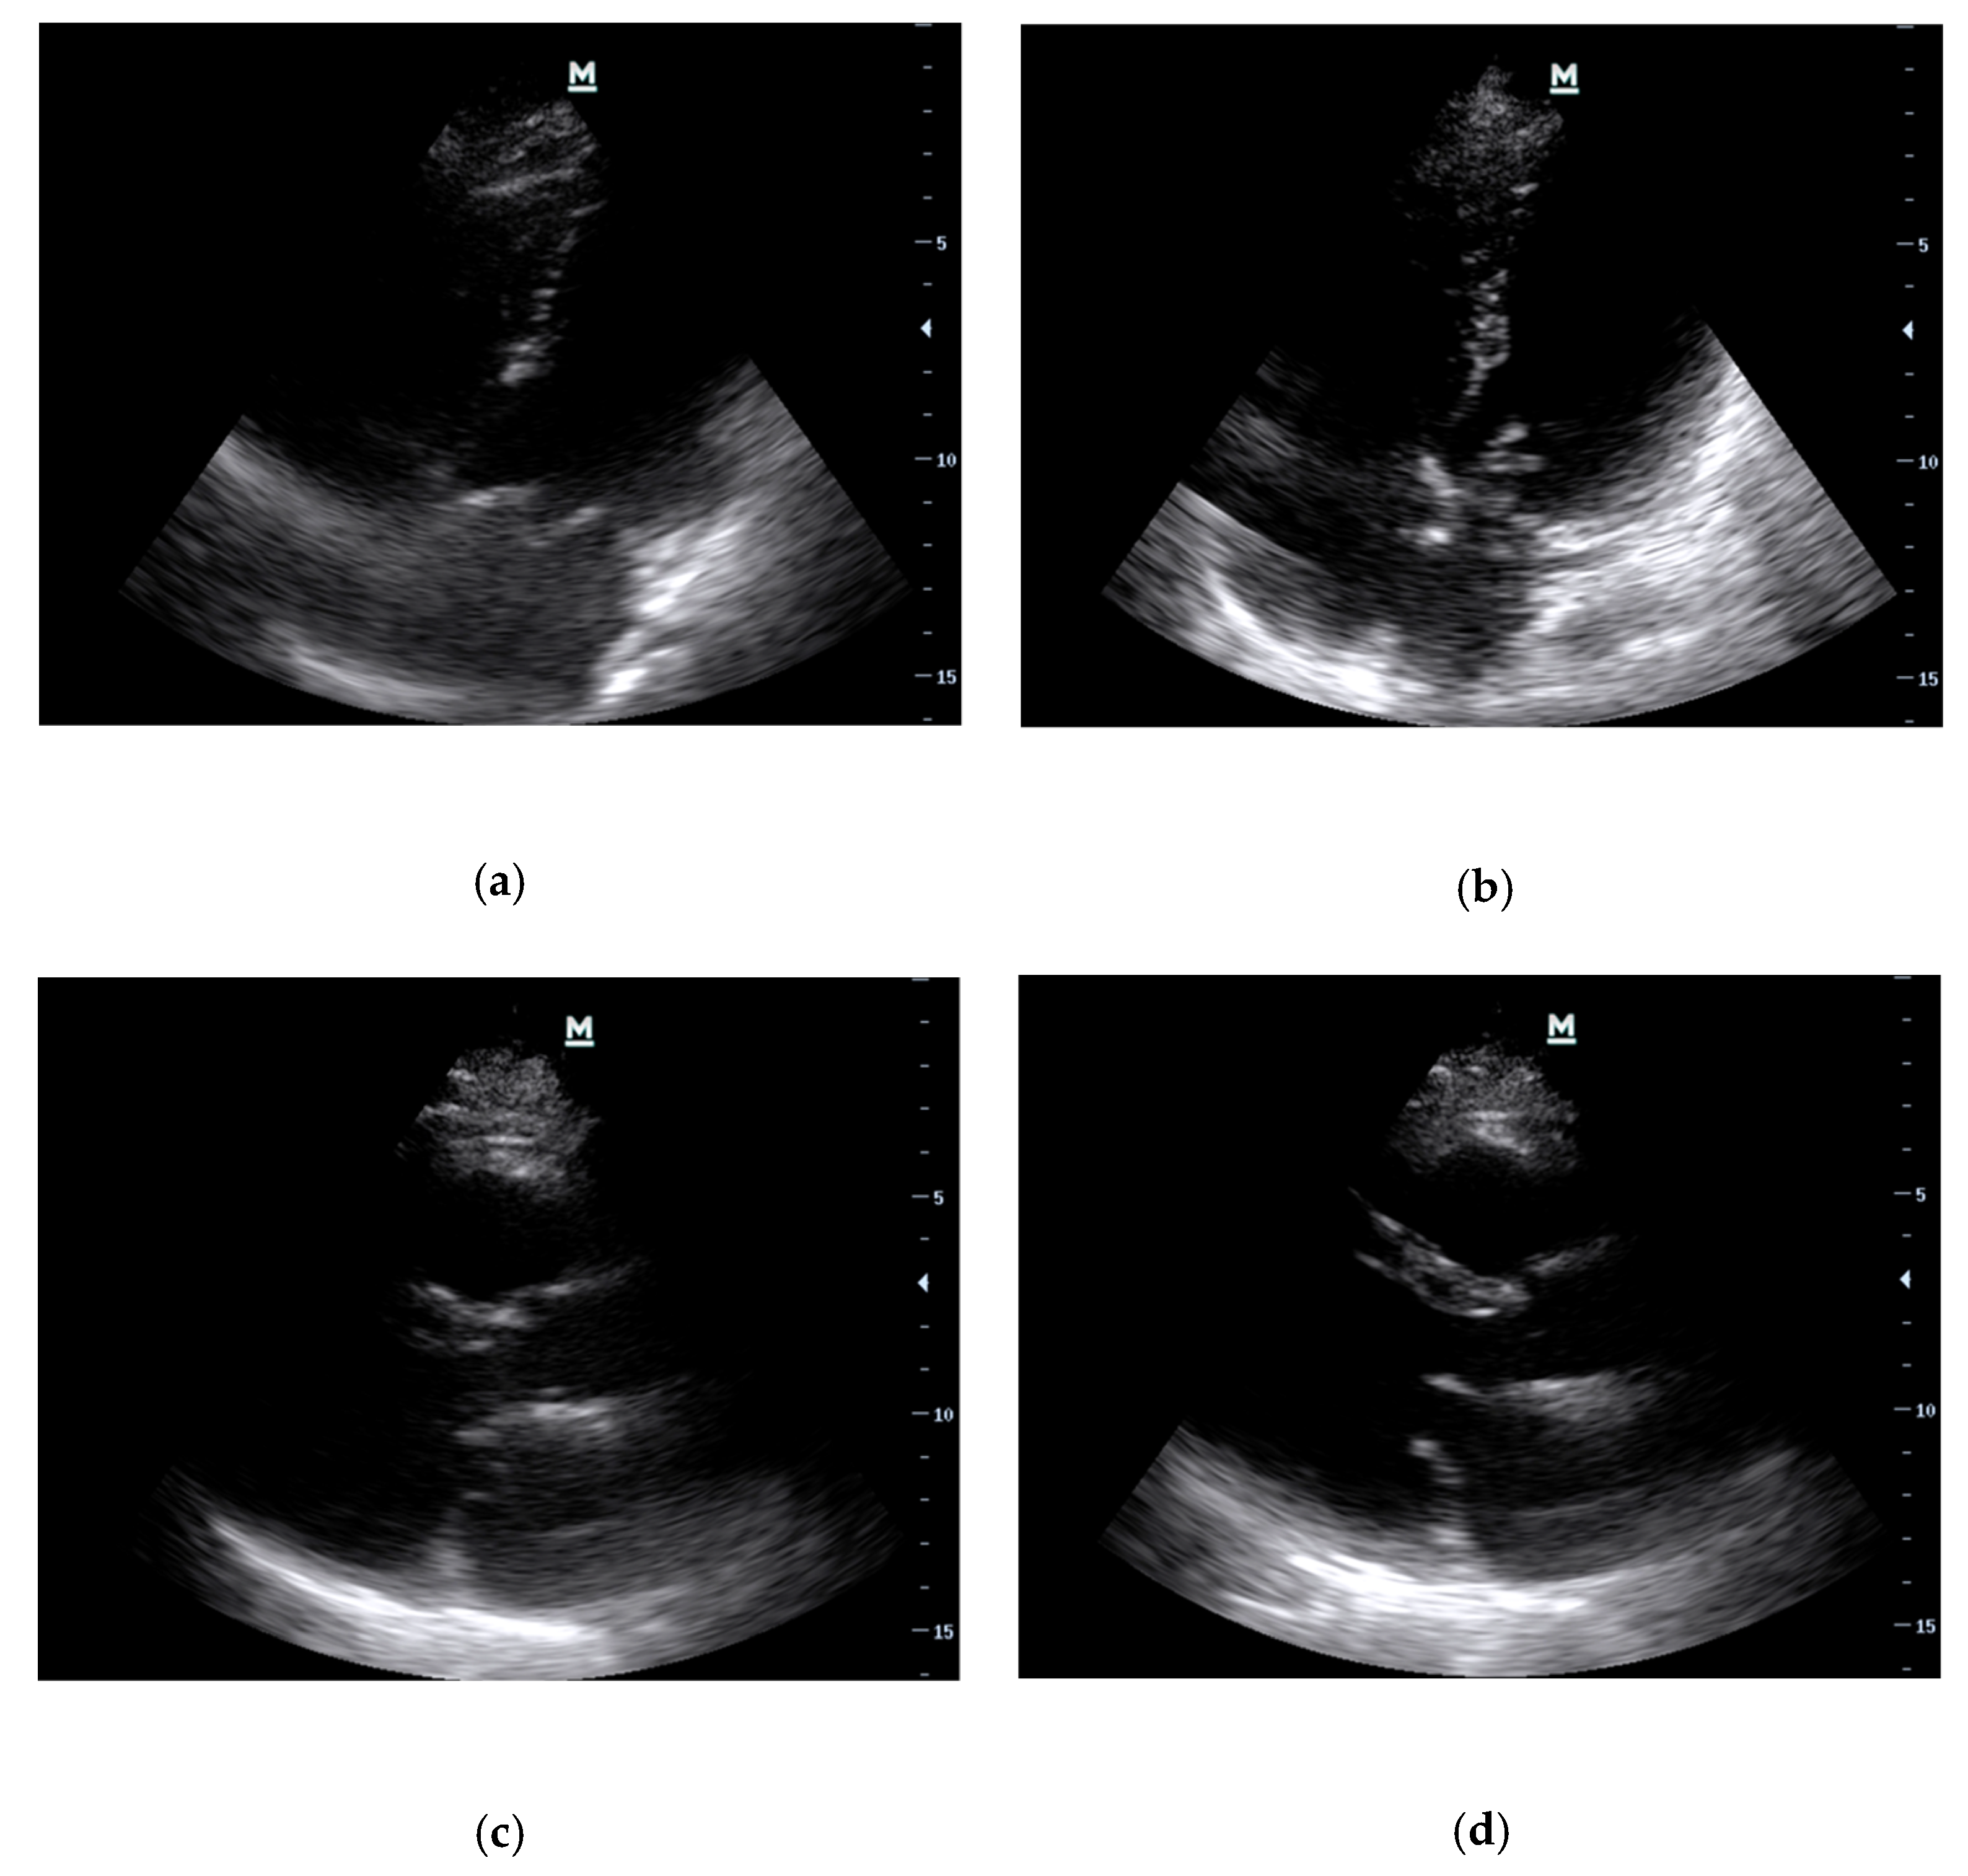

- Basic Cardiac Views (Figure 3)The standard echocardiographic views required to assess cardiac valvular structure and function include the parasternal long-axis (PLAX), parasternal short-axis (PSAX), apical four-chamber (A4C) and subcostal (SC) views. These views facilitate the visualisation of the aortic, mitral, tricuspid, and pulmonic valves, thus enabling the identification of valvular abnormalities [38].